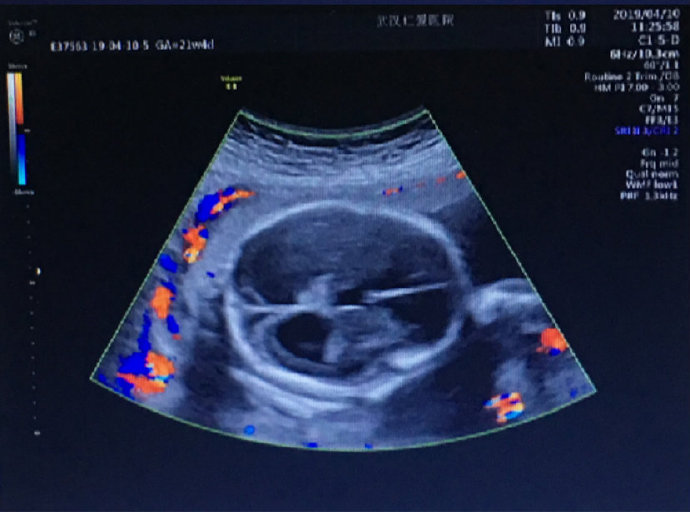

這位孕媽姓劉,家住漢陽,今年24歲,孕22周。前幾日在武漢仁愛醫(yī)院做產(chǎn)檢時,被醫(yī)生告知胎兒重度腦積水。聽到這個震驚的消息,劉女士內(nèi)心難受不已。

武漢仁愛醫(yī)院超聲影像科王娟主任介紹:“很多初次懷孕,尤其是意外懷孕的女性因為沒有懷孕經(jīng)驗,甚至不會往懷孕方面去想。當她們因為懷孕而出現(xiàn)頭痛、體溫升高、犯困、身體乏力、食欲不振等早孕癥狀時常常會誤認為自己生病了而誤服藥物,這些藥物對胎兒的傷害是特別大的,尤其是在懷孕3個月之內(nèi),這個時期是胎兒發(fā)育最活躍的時期,必須在醫(yī)生引導下謹慎用藥。”